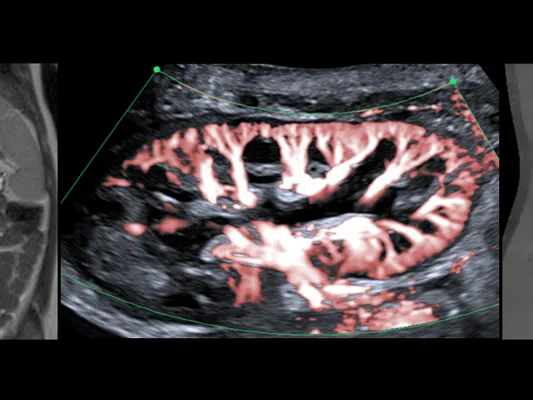

The main purpose of this diagnostic imaging fellowship is to provide you with the tools to deal with urgent and complex paediatric cases while working as a general radiologist or 1st-2nd year paediatric radiologists. You will dive through a series of concise lectures followed by case demos and discussions that will give you an overview of cases you should not miss.

We will learn about paediatric tumours and tumour-like lesions, life-threatening paediatric emergencies, liver, and kidney transplant complications, and from radiological mistakes that could cause a negative medical outcome to children.

• Lectures on paediatric ultrasound, CT, and MRI